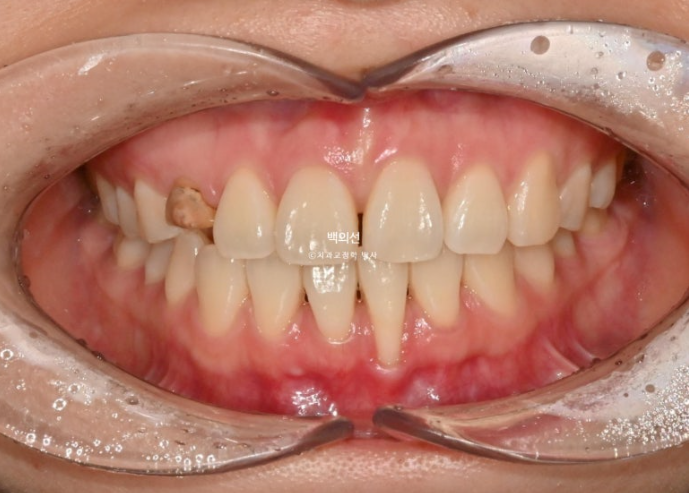

작년 가을 교정치료를 위해 내원한 환자분입니다.

오래 전 교정치료를 이미 받은 상태로 철사유지장치가 붙어있는 상태에서 오셨습니다.

아래 앞니 하나가 뿌리가 바깥으로 나가면서 잇몸퇴축이 심합니다.

잔존유치는 영구치 송곳니가 매복되는 바람에 남아있는 상태입니다.

잔존유치의 뿌리가 썩 튼튼하지는 않으나, 동요도는 전혀 없어 쓸때까지 쓰기로 합니다.

그런데 잔존유치에 교정력을 가할경우, 안그래도 약한 유치 뿌리가 녹을 수 있어서 잔존유치는 치료기간 내내 치아이동 없이 위치 잠금으로 계획해야 하고 어태치먼트조차 붙이지 않는 게 좋습니다.

색이 어두운 치아는 잔존유치에 레진을 덮어놓은 상태이고 이번기회에 재교정을 하면서 이 치아도 변색된 레진을 제거하고 라미네이트든 크라운이든 깔끔하게 치료를 원하셨습니다.